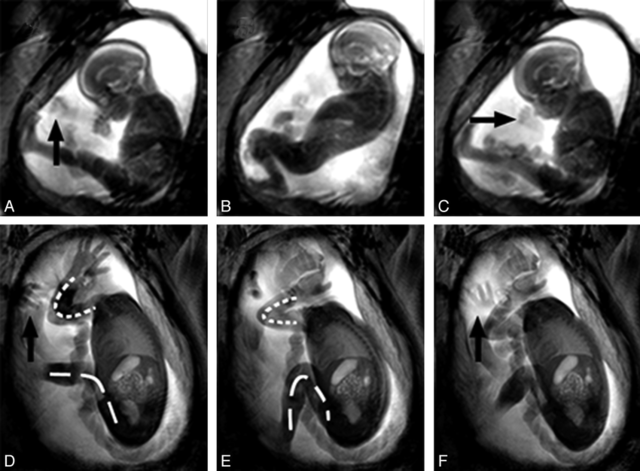

Between 12 to 14 weeks the mother will begin to hear the baby's heartbeat with a doppler ultrasound